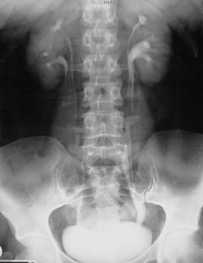

Подковообразная почка встречается чаще других и представляет собой увеличение одного из полюсов почки, в 90% - нижнего. Нередко меняется и положение подковообразной почки, которая может быть смещена медиально или даже на противоположную сторону. Подковообразная почка видна при любом виде исследования - внутривенной урографии , УЗИ, КТ, МРТ почек или сцинтиграфии.

Внутривенная урография. Подковообразная левая почка.

Подковообразная почка

Подковообразная почка - это врожденная аномалия, при которой обе почки сращиваются между собой в области нижнего или верхнего полюса с образованием перешейка. Патология часто осложняется пиелонефритом, мочекаменной болезнью, гидронефрозом и другими заболеваниями мочевыделительной системы. В используется УЗИ, урография, пиелография, компьютерная томография почек. Хирургическое лечение показано при развитии в измененной почке урологического заболевания, требующего оперативной тактики.

Подковообразная почка встречается в современной урологии с частотой 10-15% от всех почечных аномалий, в соотношении 1 случай на 500 новорожденных, причем у мальчиков в 2,5 раза чаще, чем у девочек. Порок характеризуется сращением почек в области нижних, реже - верхних полюсов, в результате чего соединенные почки приобретают «U»-образный вид, напоминающий подкову. При этом каждая из почек имеет свой мочеточник, впадающий в мочевой пузырь, и питающие сосуды. В 88,6% подковообразные почки имеют аномальное кровообращение и необычное строение чашечек.

План диагностического обследования включает УЗИ, УЗДГ, экскреторную урографию либо ретроградную пиелографию, почечную артериографию, сцинтиграфию, компьютерную томографию. Урограммы позволяют рассмотреть низкое расположение органа, ограниченную подвижность, наслоение теней нижних полюсов почки на контур позвоночного столба, тень перешейка. При ретроградной пиелографии в первые минуты визуализируется четкий силуэт подковообразной почки и ее перешейка, низкое положение почечных лоханок, аномальное расположение чашечек.

При УЗИ почек определяется отсутствие смещаемости почечных контуров, нетипичное расположение почечных лоханок и измененная форма чашечек; при УЗДГ выявляется аномальное кровоснабжение подковообразной почки. Выполнение нефросцинтиграфии фиксирует характерное накопление радионуклидного препарата в виде подковы, огибающей позвоночный столб. Почечная ангиография выполняется для исследования сосудистой архитектоники, определения количества, локализации и наличия дополнительных сосудов, толщины и васкуляризации перешейка, что имеет важное значения при планировании операции.

В процессе УЗИ почек может быть выявлено нетипичное расположение почечных лоханок, аномальная форма чашечек, при допплерографии обнаруживается аномальное кровоснабжение такой почки. Урография позволяет определить нетипичное расположение органа, тень перешейка и наслоение тканей почки на контур позвоночного столба. Ретроградная пиелография позволяет визуализировать подковообразную форму почки пациента и различные аномалии анатомического строения почки.